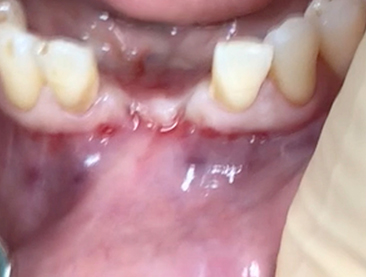

A clinical case using resorbable membrane

• A clinical case using resorbable membrane 3